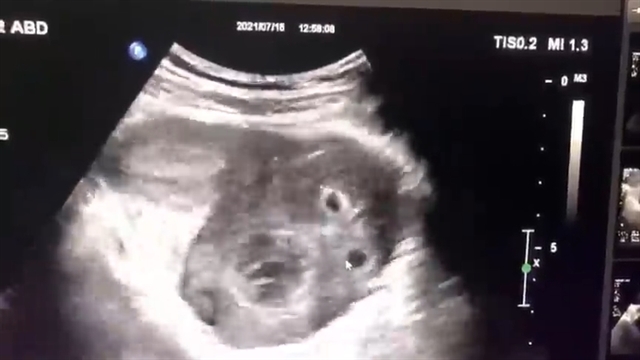

مراجعه کننده دختر خانم 13 ساله ای می باشد که دچار درد شدید شکم شده است، در سونوگرافی رحم و تخمدان مشاهده می کنید که تخم دان سمت چپ به شدت بزرگ شده است که دلیل آن وجود کیست می باشد.